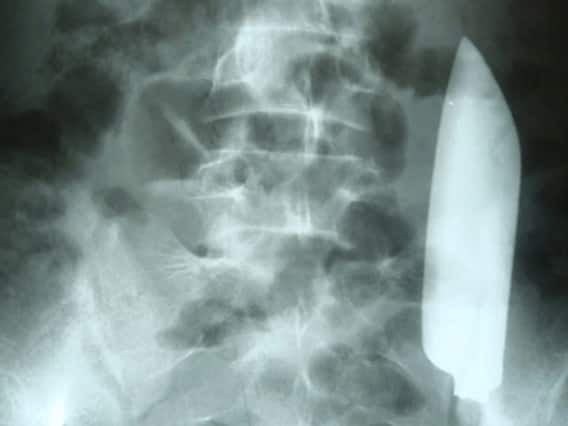

Nepal Viral News: नेपाल में एक हैरान करने वाला मामला सामने आया है. यहां रहने वाले एक 22 साल के युवक के पेट से चाकू निकला है. युवक के पेट में 15 सेंटीमीटर लंबा चाकू देख डॉक्टरों के भी होश उड़ गए. मीडिया रिपोर्ट के अनुसार इस बात का खुलासा तब हुआ जब युवक को पेट दर्द हुआ और वह इलाज के लिए अस्पताल गया.

न्यूजवीक की रिपोर्ट के अनुसार युवक पेट दर्द की शिकायत लेकर अस्पताल गया. जब डॉक्टरों ने उसके पेट पर मिले एक घाव के निशान के बारे में पूछा तो वह स्पष्ट जवाब नहीं दे पाया. इसके बाद डॉक्टरों ने दर्द का कारण जानने के लिए युवक का अल्ट्रासॉउन्ड किया. अल्ट्रासॉउन्ड रिपोर्ट देख सभी के होश उड़ गए. दरअसल, युवक के पेट में 15 सेंटीमीटर चाकू दिखाई दिया.

लड़ाई के दौरान पेट में गया था चाकू आनन फानन में युवक की सर्जरी की गई, जिसके बाद चाकू को पेट से बाहर निकाला गया. फिलहाल युवक खतरे से बाहर है. रिपोर्ट के अनुसार युवक ने बाद में डॉक्टरों को बताया कि उसकी कुछ दिनों पहले लड़ाई हुई थी, जिसमें उसे चाकू लगा था. उस समय युवक ने स्थानीय डॉक्टर से इलाज कराया था, जिसने घाव पर टांके लगा दिया था.

युवक के मुताबिक यह सब कुछ जब हुआ था तो वह शराब के नशे में था. ऐसे में उसे आभास नहीं हुआ कि चाकू का जख्म कितना गहरा है. डॉक्टरों का अनुमान है कि इस घटना के दौरान ही चाकू युवक के पेट में चला गया था. बाद मेंं टांकों की वजह से घाव भर गया था और फिर सूख भी गया. इसलिए हेल्थ वर्कर ने उसे डिस्चार्ज कर घेर भेज दिया था.

युवक अब पूरी तरह ठीक डॉक्टरों ने जांच के बाद कहा कि युवक को न ही दस्त, न उल्टी और न ही कब्ज का एहसास हो रहा था. उसका ब्लड सर्कुलेशन भी सामान्य था. यह वाकई हैरान करने वाला है. हैरानी की बात यह थी कि चाकू पेट में था, लेकिन उससे किसी अंग को नुकसान नहीं पहुंचा था. डॉक्टरों ने कहा कि युवक के पूरी तरह से ठीक होने की उम्मीद है.